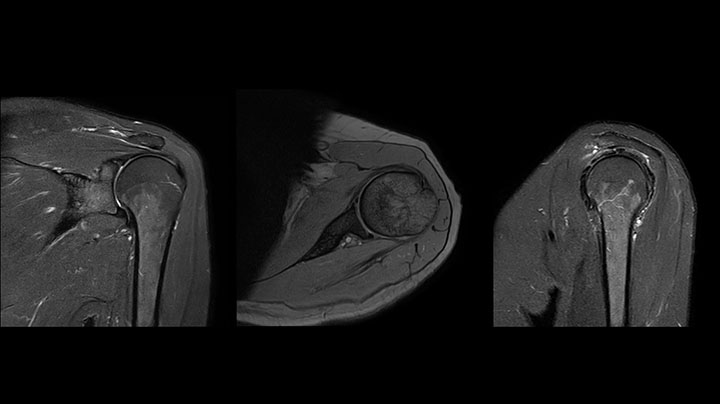

Clinical cases from Radiology Schiffer

Shoulder MRI with high quality, large coverage

The Prodiva shoulder coil is very flexible and has large coverage, which makes good positioning easier, and that contributes to the superb image quality and high SNR that we get in our shoulder exams.

Scan time 2:55 min, FOV 160 mm, acq voxels 0.55 x 0.83 x 3.0 mm.

Scan time 4:19 min, FOV 160 mm, acq voxels 0.55 x 0.80 x 3.0 mm.

Scan time 2:50 min, FOV 160 mm, acq voxels 0.70 x 0.99 x 3.0 mm.

Shoulder MRI with high quality, large coverage

The Prodiva shoulder coil is very flexible and has large coverage, which makes good positioning easier, and that contributes to the superb image quality and high SNR that we get in our shoulder exams.

Scan time 2:55 min, FOV 160 mm, acq voxels 0.55 x 0.83 x 3.0 mm.

Scan time 4:19 min, FOV 160 mm, acq voxels 0.55 x 0.80 x 3.0 mm.

Scan time 2:50 min, FOV 160 mm, acq voxels 0.70 x 0.99 x 3.0 mm.